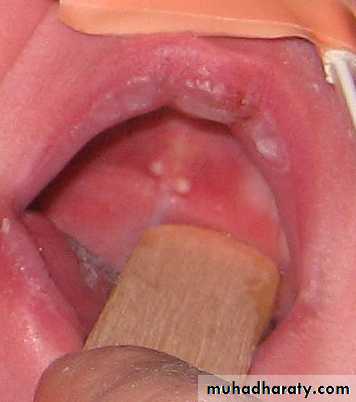

Dental lamina cyst of the newborn( Bohn's nodule).Up to 80% of newborn infants have small nodules or cyst in the gingiva due to proliferation of epithelial rest of serres.

Resolve spontaneously.

cyst ( Epstein pearl ) may arise from the non odontogenic epithelium along the midpalatal raphe, may enlarge sufficiently to appear as creamy- colourd swelling a few millimeters in diameter, but also resolve spontaneously in a matter of months.